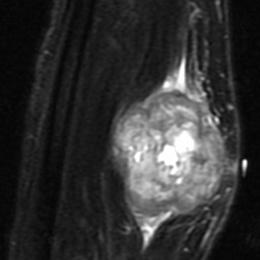

Liposarcoma is a malignant (cancerous) soft-tissue tumor that most commonly affects the extremities or the abdomen. They are the second most common soft-tissue sarcoma.